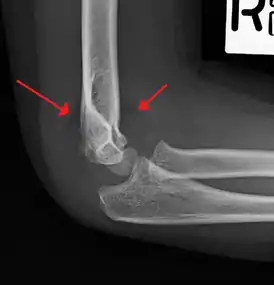

A supracondylar humerus facture is diagnosed by x-ray and the injured limb will be examined to assess the surrounding soft tissue, neurovascular status, and to identify any other injuries to the affected area.[5] Pain, swelling, and deformity near the elbow or arm area is common and a bleed near the fracture may result in an effusion in the elbow joint. With severe displacement, there may be an anterior dimple from the proximal bone end trapped within the biceps muscle. The skin is usually intact. If there is a laceration that communicates with the fracture site, it is an open fracture, which increases infection risk. For fractures with significant displacement, the bone end can be trapped within the biceps muscle with resulting tension producing an indentation to the skin, which is called a "pucker sign".

Diagnosis is confirmed by x-ray imaging. Antero-posterior (AP) and lateral view of the elbow joint should be obtained. Any other sites of pain, deformity, or tenderness should warrant an X-ray for that area too. X-ray of the forearm (AP and lateral) should also be obtained for because of the common association of supracondylar fractures with the fractures of the forearm. Ideally, splintage should be used to immobilise the elbow at 20 to 30 degrees flexion in order to prevent further injury of the blood vessels and nerves while doing X-rays. Splinting of fracture site with full flexion or extension of the elbow is not recommended as it can stretch the blood vessels and nerves over the bone fragments or can cause impingement of these structures into the fracture site.[3]

On lateral view of the elbow, there are five radiological features should be looked for: tear drop sign, anterior humeral line, coronoid line, fish-tail sign, and fat pad sign/sail sign (anterior and posterior).[3][8]

Fat pad sign/sail sign - A non-displaced fracture can be difficult to identify and a fracture line may not be visible on the X-rays. However, the presence of a joint effusion is helpful in identifying a non-displaced fracture. Bleeding from the fracture expands the joint capsule and is visualized on the lateral view as a darker area anteriorly and posteriorly, and is known as the sail sign.[8]